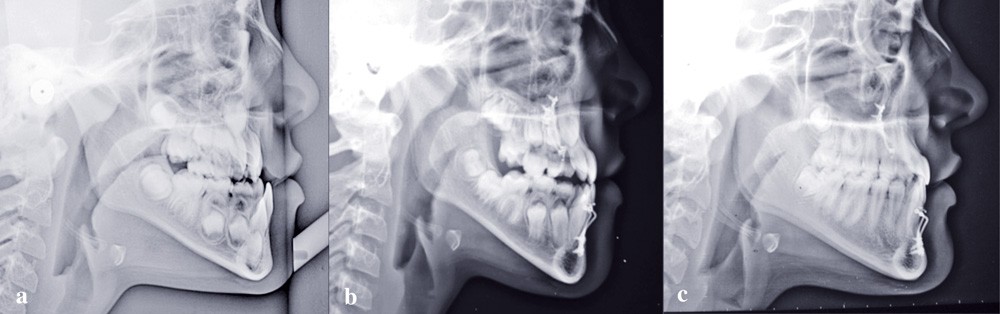

Si l’on analyse le résultat du point de vue squelettique, on constate une belle amélioration orthopédique du prémaxillaire, stable dans le temps. La croissance maxillaire a heureusement été toujours supérieure à la forte croissance mandibulaire. On note après orthopédie un bon support osseux pour la lèvre supérieure qui présente une meilleure épaisseur. À la fin de la croissance, les courbures naso-labiale et labio-mentonnière sont optimisées (fig. 5).

Les téléradiographies de profil confirment la croissance du maxillaire avec une légère tendance rotationnelle antérieure et une avancée du point A de 8 mm. La croissance mandibulaire est homothétique sauf dans la région du point B où elle est freinée (fig. 6-7).